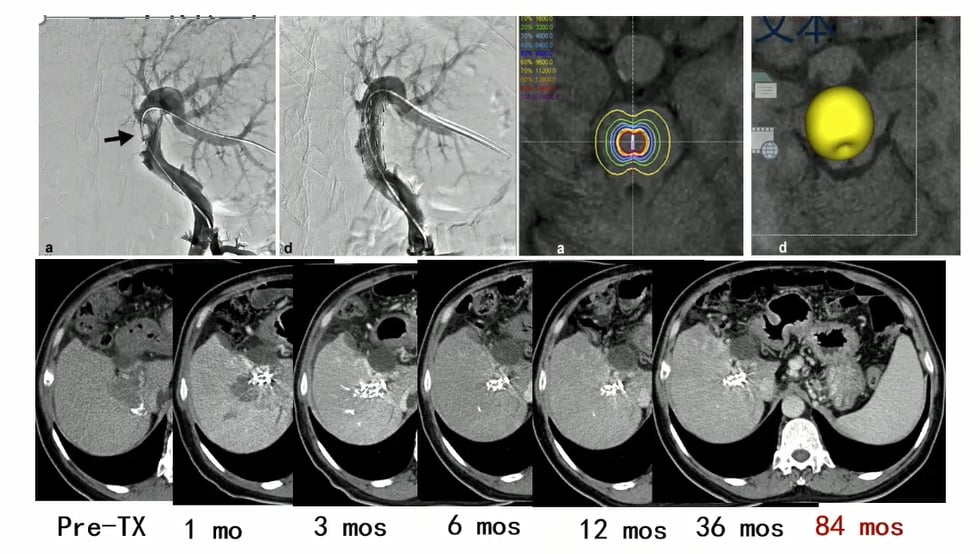

在肝细胞癌治疗中,剂量是否足够非常关键。已有研究提示,个体化高剂量策略与更好的病理坏死率、影像学应答和组织学应答相关。简单理解就是:钇90的疗效,往往高度依赖剂量学设计是否精准。

部分肝细胞癌患者在钇90后可见明显影像学缓解。

部分病例中,钇90不仅缩瘤,还可能为后续转化治疗争取机会。